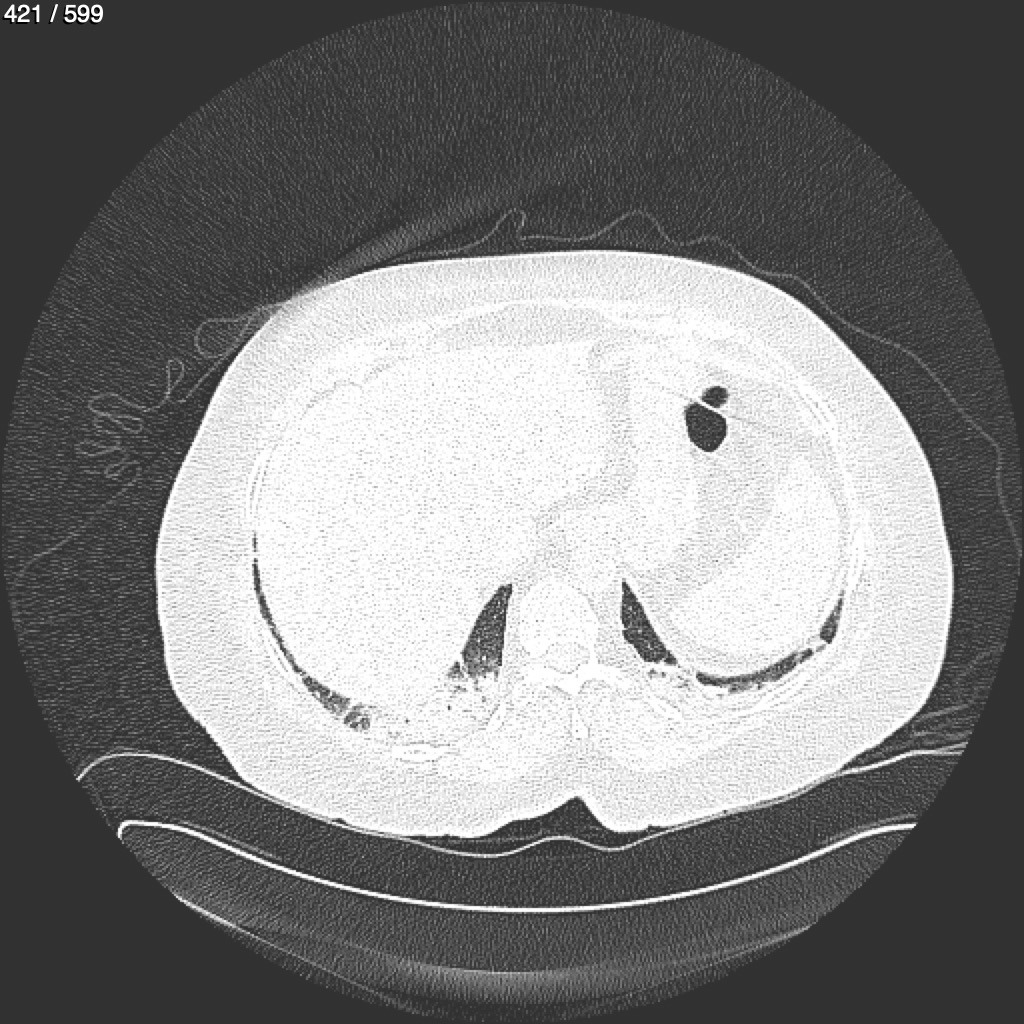

Home G​l​o​r​i​a​ ​G​l​a​d​y​s​ ​B​e​a​s​l​e​y​ ​-​ ​T​ó​r​a​x​ ​T​o​r​a​x​_​S​i​m​p​l​e​ ​(​A​d​u​l​t​o​)